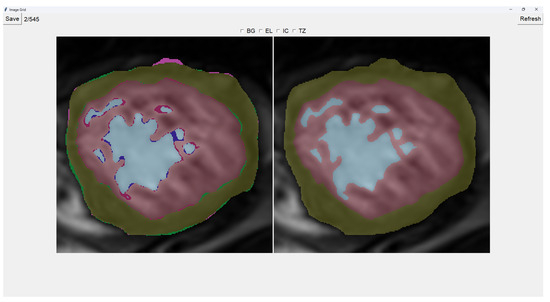

This program presents two images as shown in Figure 3. The image on the left is obtained from our previous method (QLVTHC), while the one on the right is obtained from our neural networks (Section 2.1). The final output of our program is the segmentation on the right.

We use a muted color scheme to make the colors distinguishable for colorblind people. In the image on the right, the External Layer is olive green, the Internal Cavity is cyan, and the Trabecular Zone is rose.

On the figure on the left, we mark the differences between both segmentations. This way, where there is an External Layer on the left and something else on the right, we mark it with green. For additional Internal Cavity, we mark it with blue; for Trabeculae, we mark it with wine red; for Background, we mark it with purple.

The differences between both images can be leveraged for easy transformations of the output image. The transformation is applied to the image on the right by simply clicking one of the differences. For example, if we click a blob that is colored green on the left (meaning an additional External Layer), an External Layer will appear in that zone of the image on the right. Some of these blobs are very small, so you can select them by right-clicking and dragging over them for ease of use.

Painting directly on the output image (the image on the right) is also possible. For this, we select either BG (Background), EL (External Layer), IC (Internal Cavity), or TZ (Trabecular Zone). Then, we simply left-click where we want to paint (as shown in Figure 4).